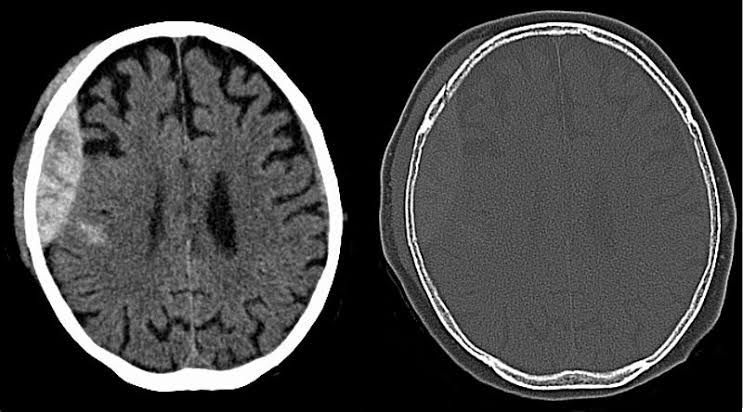

Extradural haematoma (EDH) is defined as an acute haemorrhage between the dura mater and the inner surface of the skull. An EDH can cause compression of local brain structures and a rise in intracranial pressure. If intracranial pressure continues to rise, cerebellar herniation may occur leading to brainstem death.